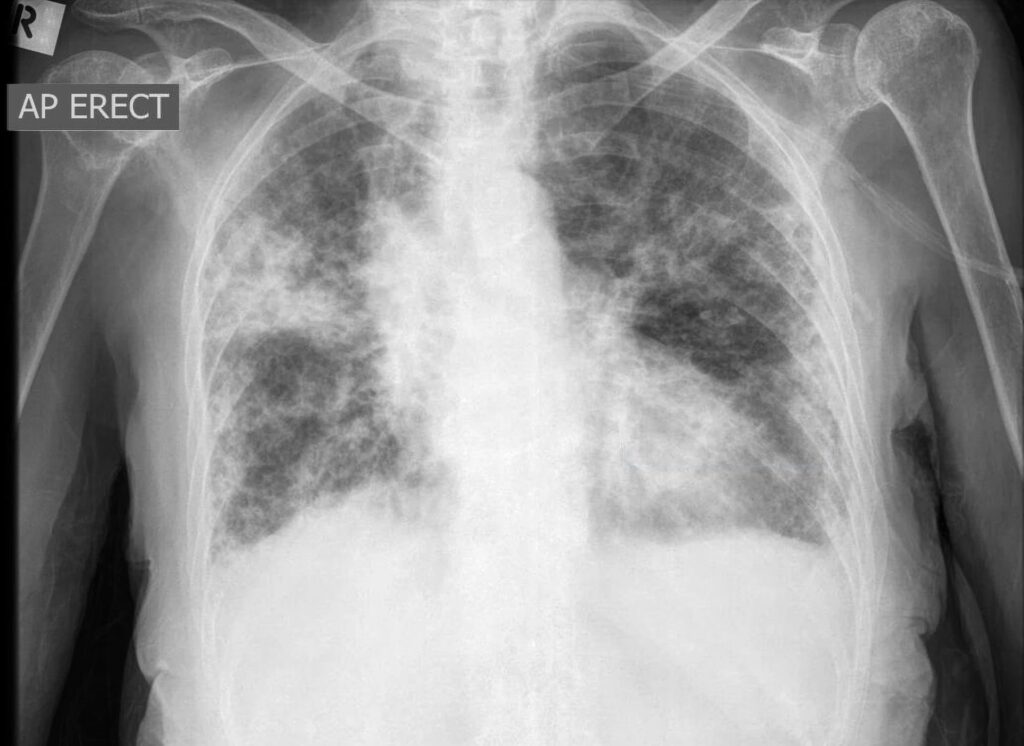

- Røntgenbillede af brystkassen: Dette er ofte den første test. Et område med konsolidering vil fremstå som et hvidt eller uigennemsigtigt (opakt) område i modsætning til det mørke, luftfyldte, raske lungevæv.